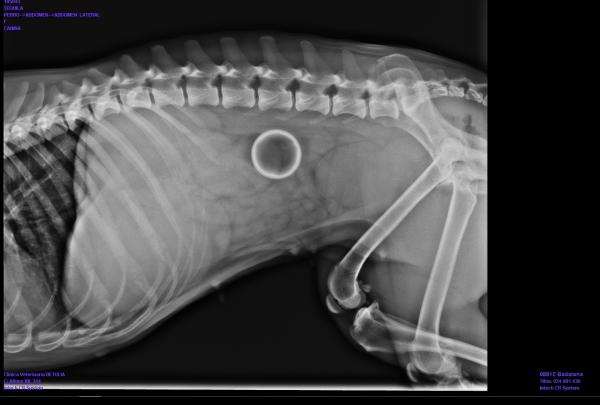

Eläinlääkäri voi havaita suoliston tukoksen koirilla vatsan röntgen. Siinä näet suoliston turvotuksen ja suuren määrän kaasua. Hoidon pitäisi loogisesti lievittää tätä estettä. Valintahoito yleensä menee läpi leikkaus ja vain eläinlääkäri voi todeta esteen ominaisuuksia tutkiessaan, onko mahdollista lievittää sitä antamalla lääkettä.